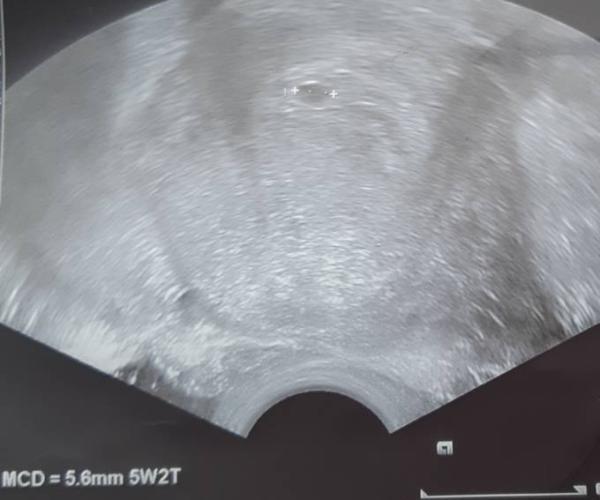

Ist zwar schlechte Qualität. Aber das war 5+2 mit Herzschlag.... lg